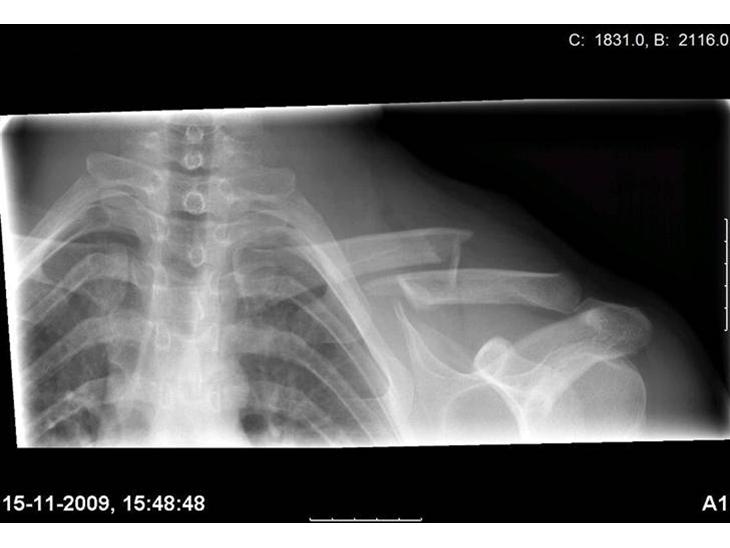

Brækket kraveben og smadret mudderchopper

Min makker og jeg var ud på en hygge offroad tur. det kostede sku et åbent kravebens brud. men jer er da heldigvis allerede i noget bedre stand nu.

Det gør pæn ondt..

har fået 2 operationer og taget skinnen ud igen....